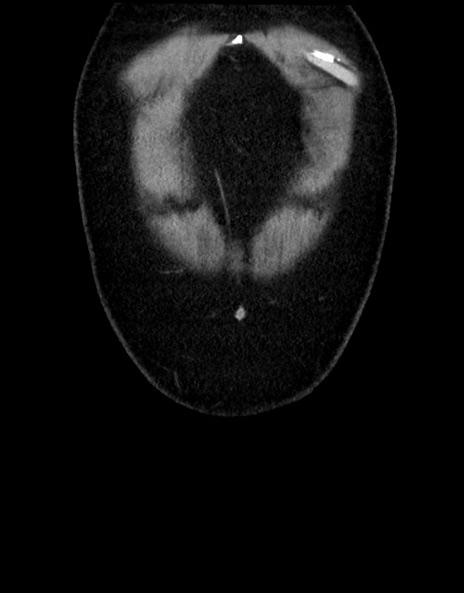

横断像

【症例】70歳代男性

【主訴】腹痛

【現病歴】今朝から腹痛あり。全体的に痛い。特に左上の方。排ガスが今日はない。冷や汗が出る。

【既往歴】直腸癌術後

【身体所見】左側腹部〜上腹部に圧痛あり。腹膜刺激症状明らかなではない。軽度反跳痛。左下腹部に術後瘢痕あり。

【データ】WBC 7700、CRP 0.02